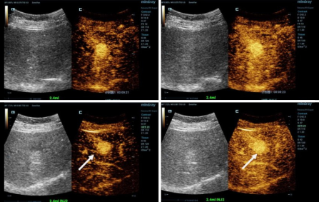

![Diagnosis yang Lebih Presisi dengan HiFR CEUS]() Diagnosis yang Lebih Presisi dengan HiFR CEUSUltrasonografi dengan kontras (CEUS) merupakan bidang yang sangat dinamis, dan dalam beberapa tahun terakhir, inovasi teknologi telah semakin meningkatkan kualitas gambar. Salah satu inovasi tersebut adalah ultrasonografi dengan kontras (CEUS) dengan frame rate tinggi (HiFR CEUS) yang dapat menghasilkan gambar hingga sepuluh kali lebih banyak daripada ultrasonografi konvensional ÔÇô dalam waktu yang bersamaan.Ultrasound | Pencitraan umum 2022-12-16

Diagnosis yang Lebih Presisi dengan HiFR CEUSUltrasonografi dengan kontras (CEUS) merupakan bidang yang sangat dinamis, dan dalam beberapa tahun terakhir, inovasi teknologi telah semakin meningkatkan kualitas gambar. Salah satu inovasi tersebut adalah ultrasonografi dengan kontras (CEUS) dengan frame rate tinggi (HiFR CEUS) yang dapat menghasilkan gambar hingga sepuluh kali lebih banyak daripada ultrasonografi konvensional ÔÇô dalam waktu yang bersamaan.Ultrasound | Pencitraan umum 2022-12-16 -